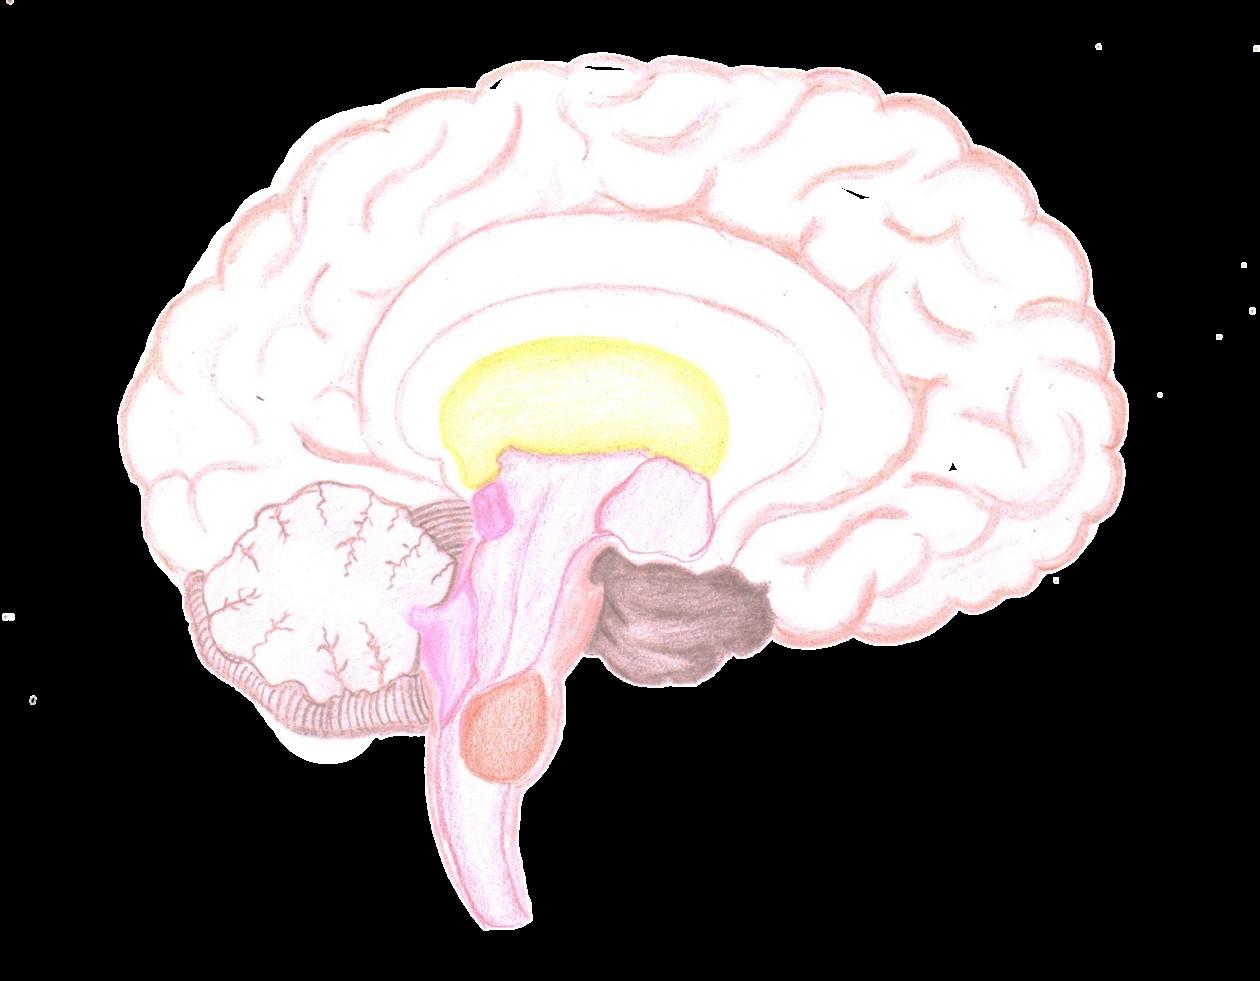

EL ENCÉFALO

HIPOTÁLAMO

CEREBELOSO BULBO

PUENTE MESENCÁFALO

Se encuentra dentro del cráneo y forma parte del sistema nervioso central. Además este órgano controla la mayoría de las actividades vitales como el sueño, hambre, sed, otros y las emociones como la alegría, tristeza, amor y mas.

HEMISFERIO CEREBRAL TÁLAMO EPITÁLAMO

Organización del Sistema Nervioso Diencefalo Tálamo

El diencéfalo constituye una de las principales estructuras del cerebro y desarrolla numerosas funciones que permiten el adecuado funcionamiento de los procesos biológicos del organismo humano.

Hipotalamo

Cerebro

Epitalamo Sub Talamo